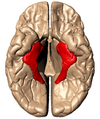

Key gyri on superior view of frontal cortex

Superior frontal gyrus

Middle frontal gyrus

Inferior frontal gyrus

Precentral gyrus

Key sulci on superior view of frontal lobe

Superior frontal sulcus

Inferior frontal sulcus

Precentral sulcus